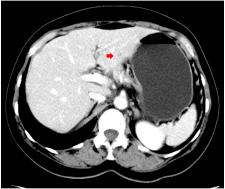

疾病复发:2025年5月7日,在辅助治疗第13个月,复查B超及CT发现肝左叶新发结节,长径约1.0厘米。行肝脏穿刺活检,病理证实为符合乳腺癌来源的转移腺癌,免疫组化与原发灶一致。

治疗近2个月后(2025年8月4日)影像学评估疗效为部分缓解,肝脏转移灶较2025年5月7日明显缩小。